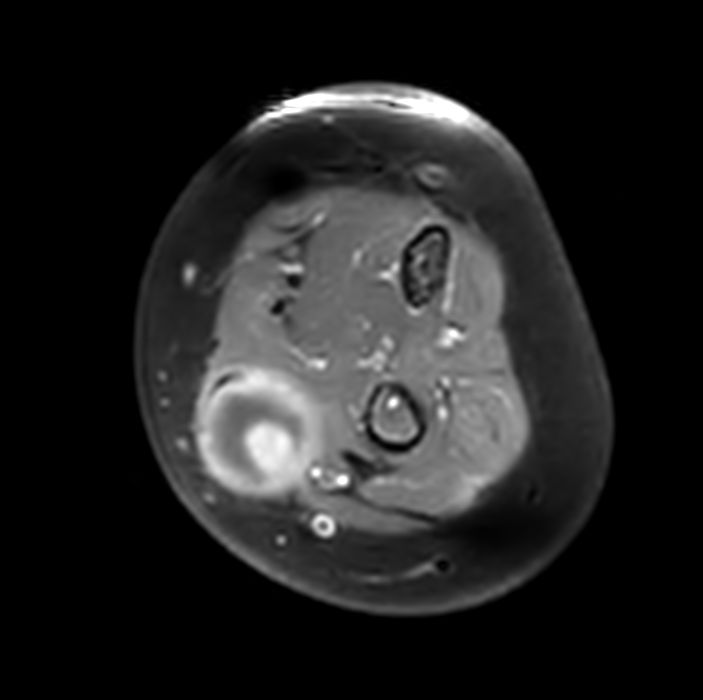

Pediatric patient with a lesion in the forearm. mDIXON XD provides uniform fat-free imaging and allows for multiple image types in one single scan. Integration of Compressed SENSE acceleration technique enables speeding up of the entire exam.

Axial T1w FatSat +gadoCompressed SENSE